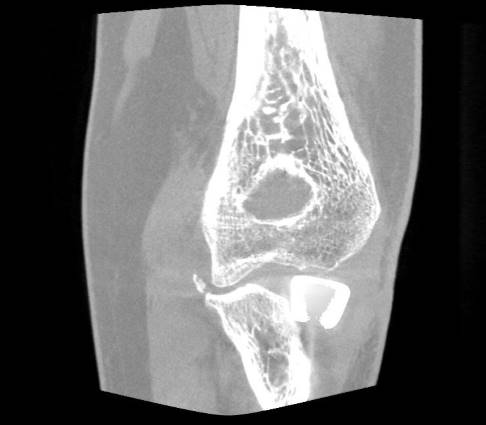

Computertomografie (CT), digitale Volumentomografie (DVT) und Magnetresonanztomografie (MRT)

Ist der Bruch nicht sicher im Röntgenbild zu beurteilen oder liegt ein komplizierter Bruch oder gar eine Zertrümmerung des Radiusköpfchens vor, erfolgt zusätzlich eine Computertomografie (CT)/digitale Volumentomografie (DVT).

Diese Untersuchungen ermöglichen eine eindeutige Einteilung des vorliegenden Bruchs und die Darstellung von möglicherweise vorhandenen knöchernen Begleitverletzungen. Der Bruch des Processus coronoideus ist ein wichtiger Hinweis für ein instabiles Ellenbogengelenk. Dieser knöcherne Vorsprung der Elle stabilisiert das Gelenk neben dem Radiuskopf nach vorne.

Begleitende Verletzungen der Gelenkkapsel oder des stabilisierenden Bandapparates werden vor allem in der Magnetresonanztomografie (MRT) optimal dargestellt.